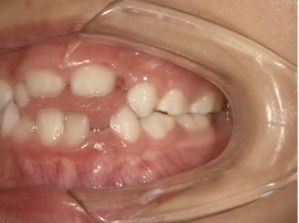

治療前① 小1:6y8m 初診

| カウンセリング・診断結果 | 前歯の生え変わり時期に来院されました。(写真①) 乳歯列期に受け口の既往があり切端咬合になりそうなため、受け口に対する矯正治療の考え方と対処法、当院のコンセプトを説明したところ治療を希望されたので診断を行いました。 診断の結果、上顎骨に対し下顎骨が長く、骨格的な構造も下顎突出型反対咬合(下顎骨が適切な位置よりも前に出ているタイプの受け口)と分かりました。 顔立ちは、中顔面が引っ込んだように見えるコンケーブに移行中です。 機能的な問題として低位舌があるため受け口の悪化が考えられることも説明し、以下の治療を提案しました。 |